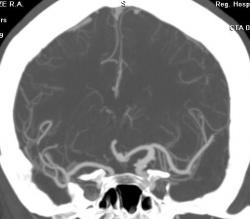

ИзображениеИзображениеИзображениеИзображениеЖенщина, 52 года. Жалобы на птоз слева. Направлена на КТ для исключения аневризмы сифона внутренней сонной артерии (ВСА). Травмы не было.

На КТ правая сонная артерия немного тоньше обычного, сифон продолжается в среднюю мозговую артерию. Правая задняя мозговая артерия отходит от основной артерии.

Левая общая сонная артерия гипертрофирована, на шейном уровне с патологической извитостью. Сифон также шире, чем справа. Задняя мозговая артерия отходит от супраклиноидного отдела ВСА - задняя трифуркация. Левая передняя мозговая артерия делится на две правую и левую передние мозговые артерии (задняя трифуркация), в развилке небольшая аневризма на широком основании. Вторая такая же аневризма на уровне отхождения глазной артерии.

Аневризмы - красные стрелки, Средние мозговые артерии - черные, Задние - зеленые, передняя мозговая - голубая стрелка.